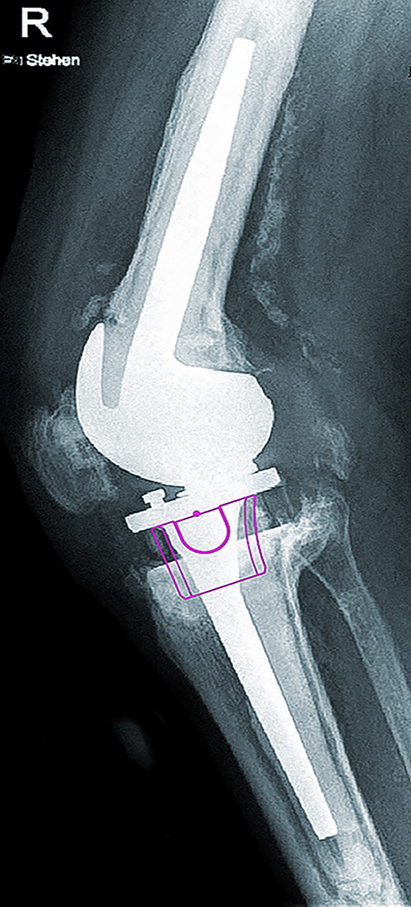

X-rays AP and lateral six weeks postoperatively: correct position of the revision prosthesis with physiological patella articulation; good press-fit of the metaphyseal tibial component; prophylactically applied securing cerclage (1, 2).

The preoperative planning was implemented intraoperatively without any restrictions. The good primary stability of the tibial hybrid cone made it possible to dispense with an additional extension of the prosthesis socket.

No postoperative complications; very good pain reduction.

Initially there were no postoperative complications. The patient was mobilized early and achieved a flexion of 90° after only a few days. The postoperative X-ray findings were normal. A hematoma infection after three weeks with the detection of Staphylococcus aureus led to dry and irritation-free wound conditions after a single wound revision with inlay change and antibiotics. Afterwards, a complication-free progress without indication of infection persistence was observed.